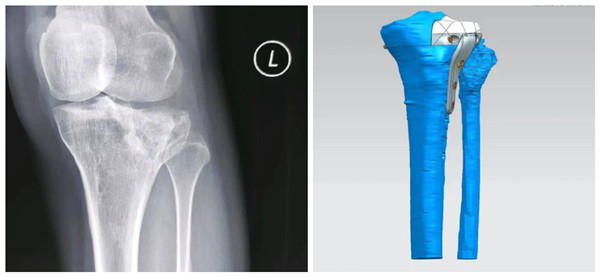

为此,在创伤骨科专家的支持下为谢女士的膝关节设计了一个全新的解决方案,即通过3D打印技术定制一个关节面与钢板一体化假体,以修复严重塌陷和骨缺损的外侧平台。

2023年12月14日谢女士了实施手术。术后,患者即刻恢复了充分的关节稳定性,全程无受限的关节屈伸活动度,随着3D打印在现代医学领域的发展和完善下与不断临床相契合,为更多此类患者提供更加精准、个体化的治疗手段和有益帮助。